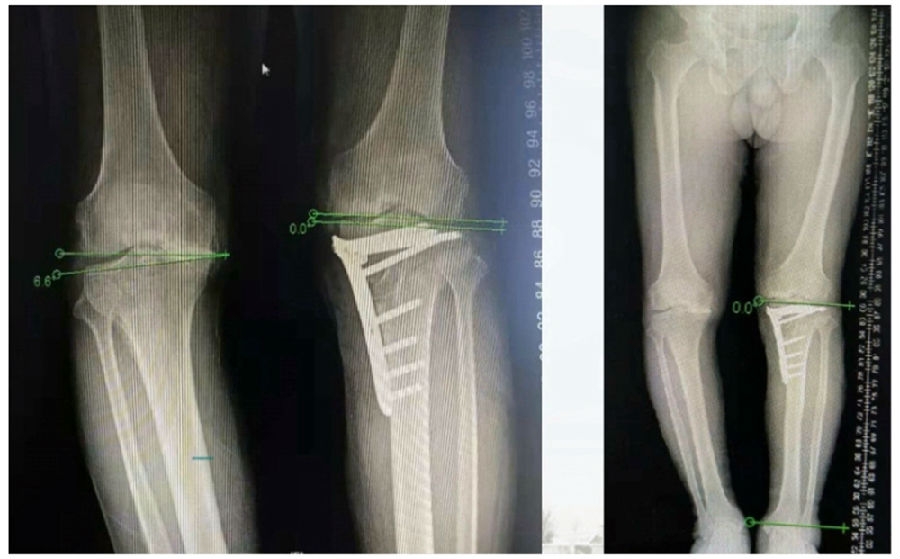

典型病例,女性,56岁,农民右膝内翻18度。

术前影像

术中影像

结合影像学来看,该患者单纯用闭合截骨或开放截骨,对肢体均有影响,所以决定采用混合型截骨。术中混合截骨旋转中心选在内外1/3处,先做闭合楔,然后顺势将开放楔敲开,达到术前设计的目标力线。术后随访力线达到要求。

术后X线